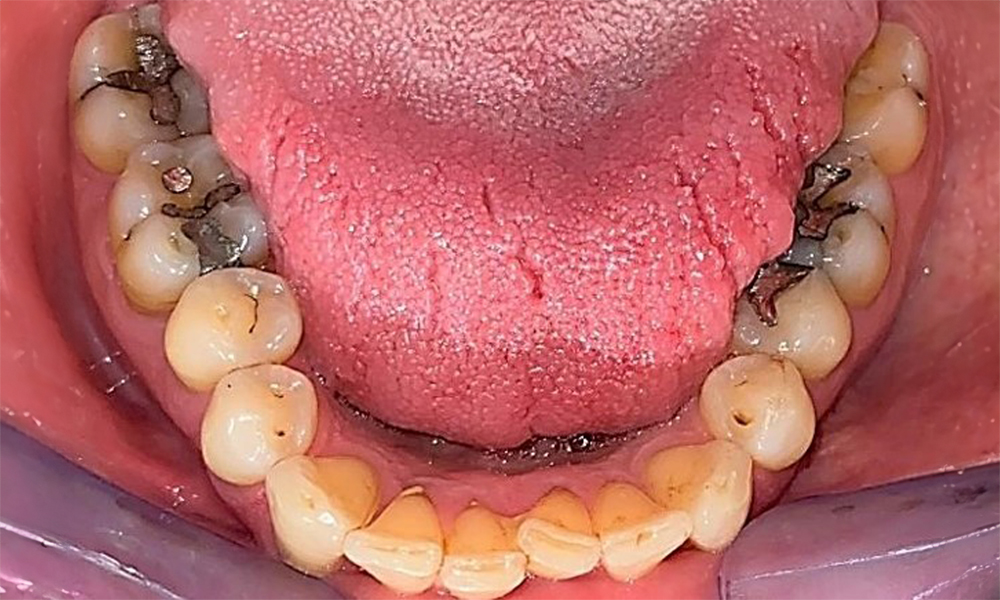

Occlusal view of the mandible showing the denture in situ.

Fig. 6 Occlusal view of the mandible showing the denture in situ. © Dr R. Krapf

The patient has a full dentition with 28 teeth, which includes amalgam and composite fillings in the molar and premolar regions. There is a visible clinical marginal gap present on tooth 14. Tooth 27 has an adequate gold inlay. There are also generalized attritions and abrasions. (Fig. 2, Fig. 3, Fig. 4, Fig. 5, Fig. 6)

Periodontal findings

The patient has stage II, grade B periodontitis (5). At 1 to 3 mm, the clinical probing depths were within the physiological range. Localized probing depths of 5 mm were observed on the mesiopalatal aspects on both 17 and 27. There are generalized recessions of 1–3 mm with partial loss of the interdental papillae (Fig. 2, Fig. 3, Fig. 4)